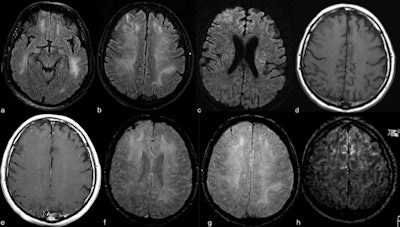

The study included 50 of 235 patients with COVID-19 admitted to the intensive care unit (ICU) between March 1 and April 18 who developed neurological symptoms. Of these 50 individuals, 27 underwent brain MRI scans (54%); 44% had acute findings. Ten of the 27 patients who had brain MRI showed cortical signal abnormality on fluid-attenuated inversion-recovery (FLAIR) protocols; three patients showed accompanying subcortical and deep white-matter signal abnormality on FLAIR images.

The researchers also found the following brain MRI results:

- Four patients had frontal lobe abnormalities, while three had abnormalities in the parietal lobe, four in the occipital lobe, one in the temporal lobe, three in the insular cortex, and three in the cingulate gyrus.

- Of 10 patients with cortical signal abnormalities, cerebrospinal fluid was sampled from five. Four of these patients had elevated total protein (mean 79.9 mg/dL).

- One patient had acute transverse sinus thrombosis and one patient had acute infarction in the right middle cerebral artery area -- both of whom did not have accompanying cortical signal abnormality.